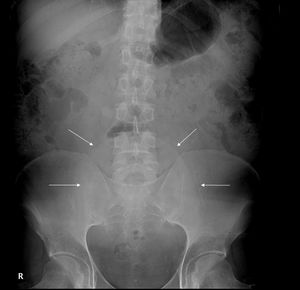

En la analítica sanguínea destacaba un fracaso renal agudo (creatinina 4,1mg/dl, urea 139mg/dl y potasio 4,8 mmol/l) con leve elevación de los reactantes de fase aguda. La radiografía de abdomen (fig. 1) mostró un globo vesical, confirmado posteriormente con ecografía que, además, reveló ectasia uretero pielocalicial bilateral grado moderado severo.